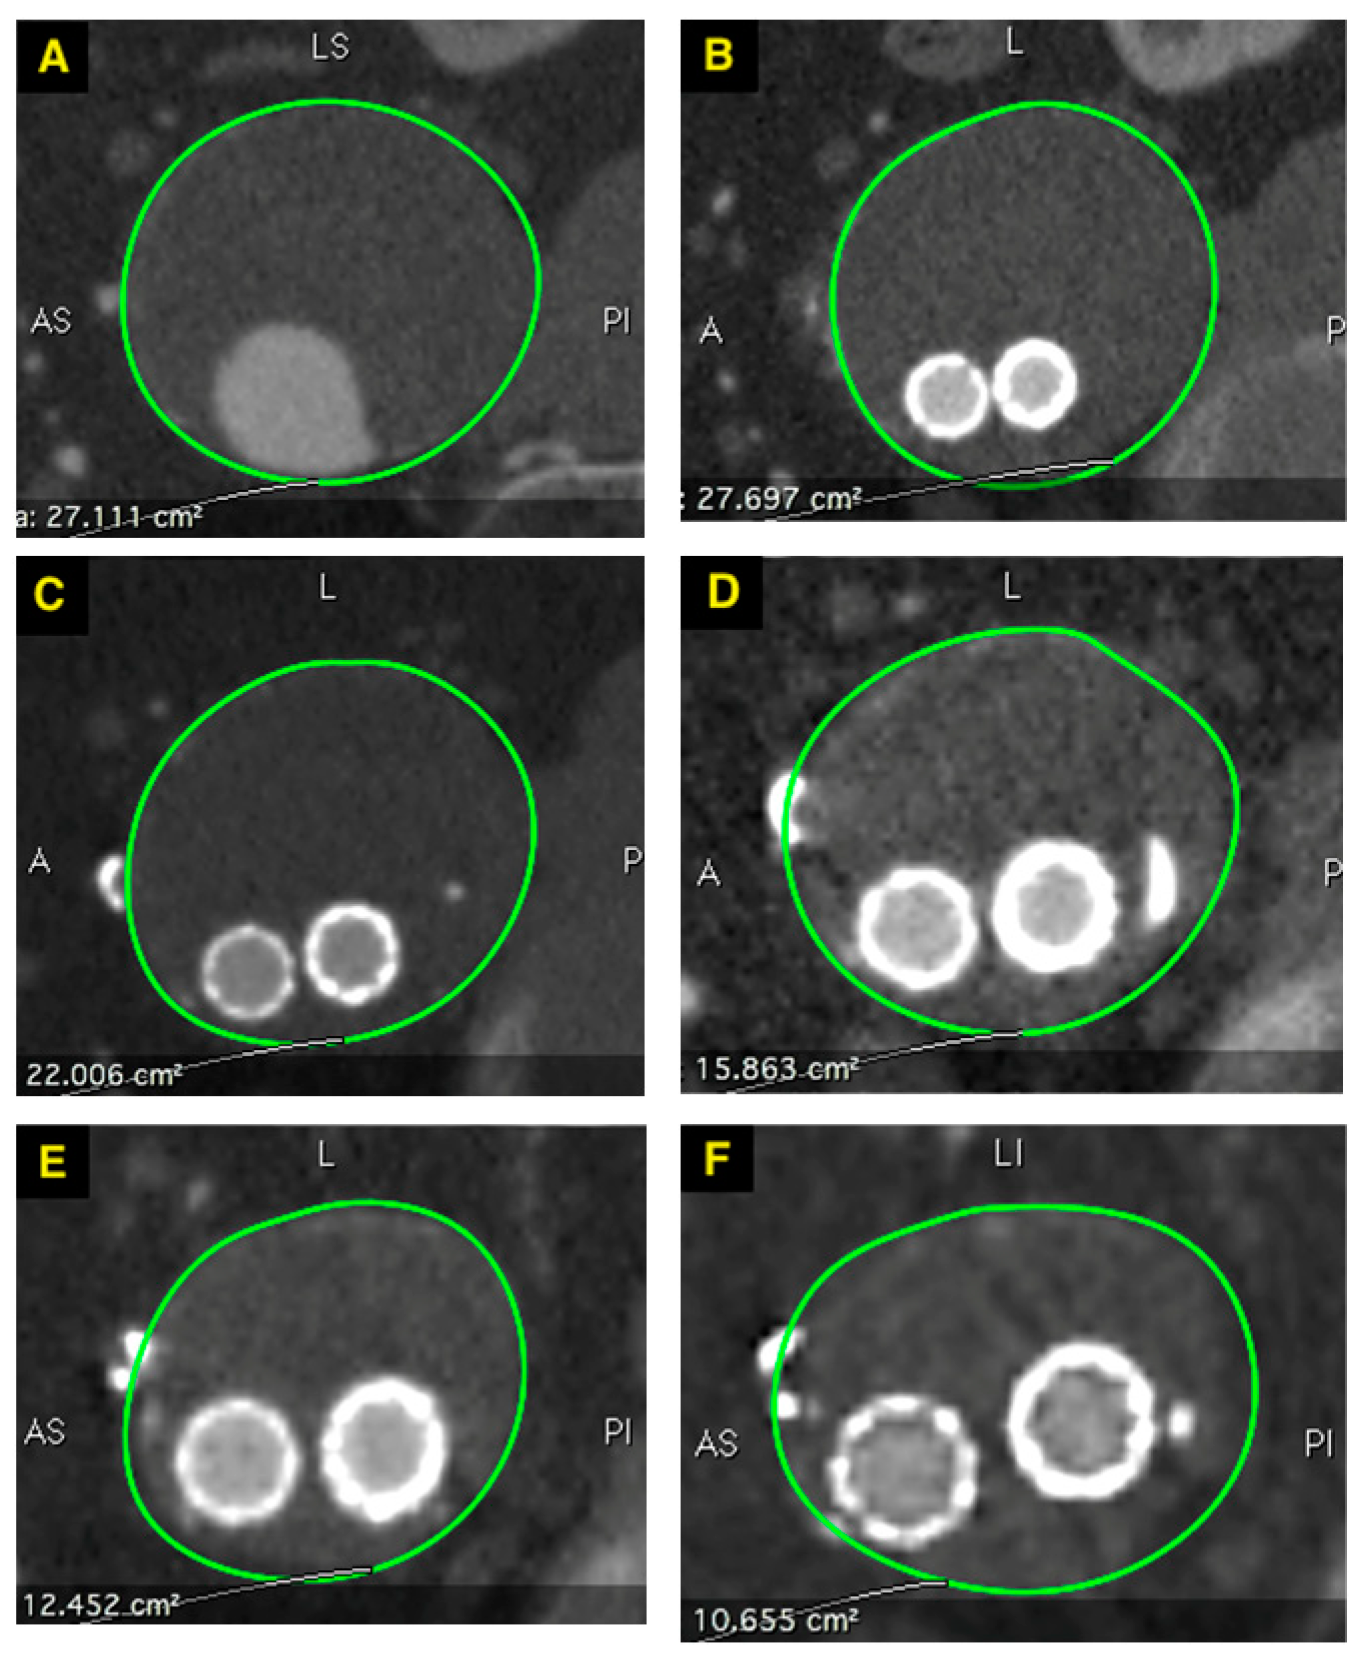

The maximum aneurysm sac growth was 6 mm, observed in 12% of patients (3/24), all of whom had a type II endoleak identified at the first-month follow-up. The mean aneurysm sac shrinkage compared to the pre-treatment diameter was 6 ± 7 mm after one year, 7 ± 11 mm after two years, and 10 ± 14 mm after three years (Figure 6). Statistically significant aneurysm sac shrinkage was observed one year after stent graft implantation (p < 0.001).

Figure 6. Changes of maximal aneurysm sac cross sectional area over time. (A)—before treatment 27.1 cm2, (B)—1st month follow-up 27.7 cm2, (C)—6th month follow-up 22.1 cm2, (D)—1st year follow-up 15.9 cm2, (E)—2nd year follow-up 12.4 cm2, (F)—3rd year follow-up 10.7 cm2.